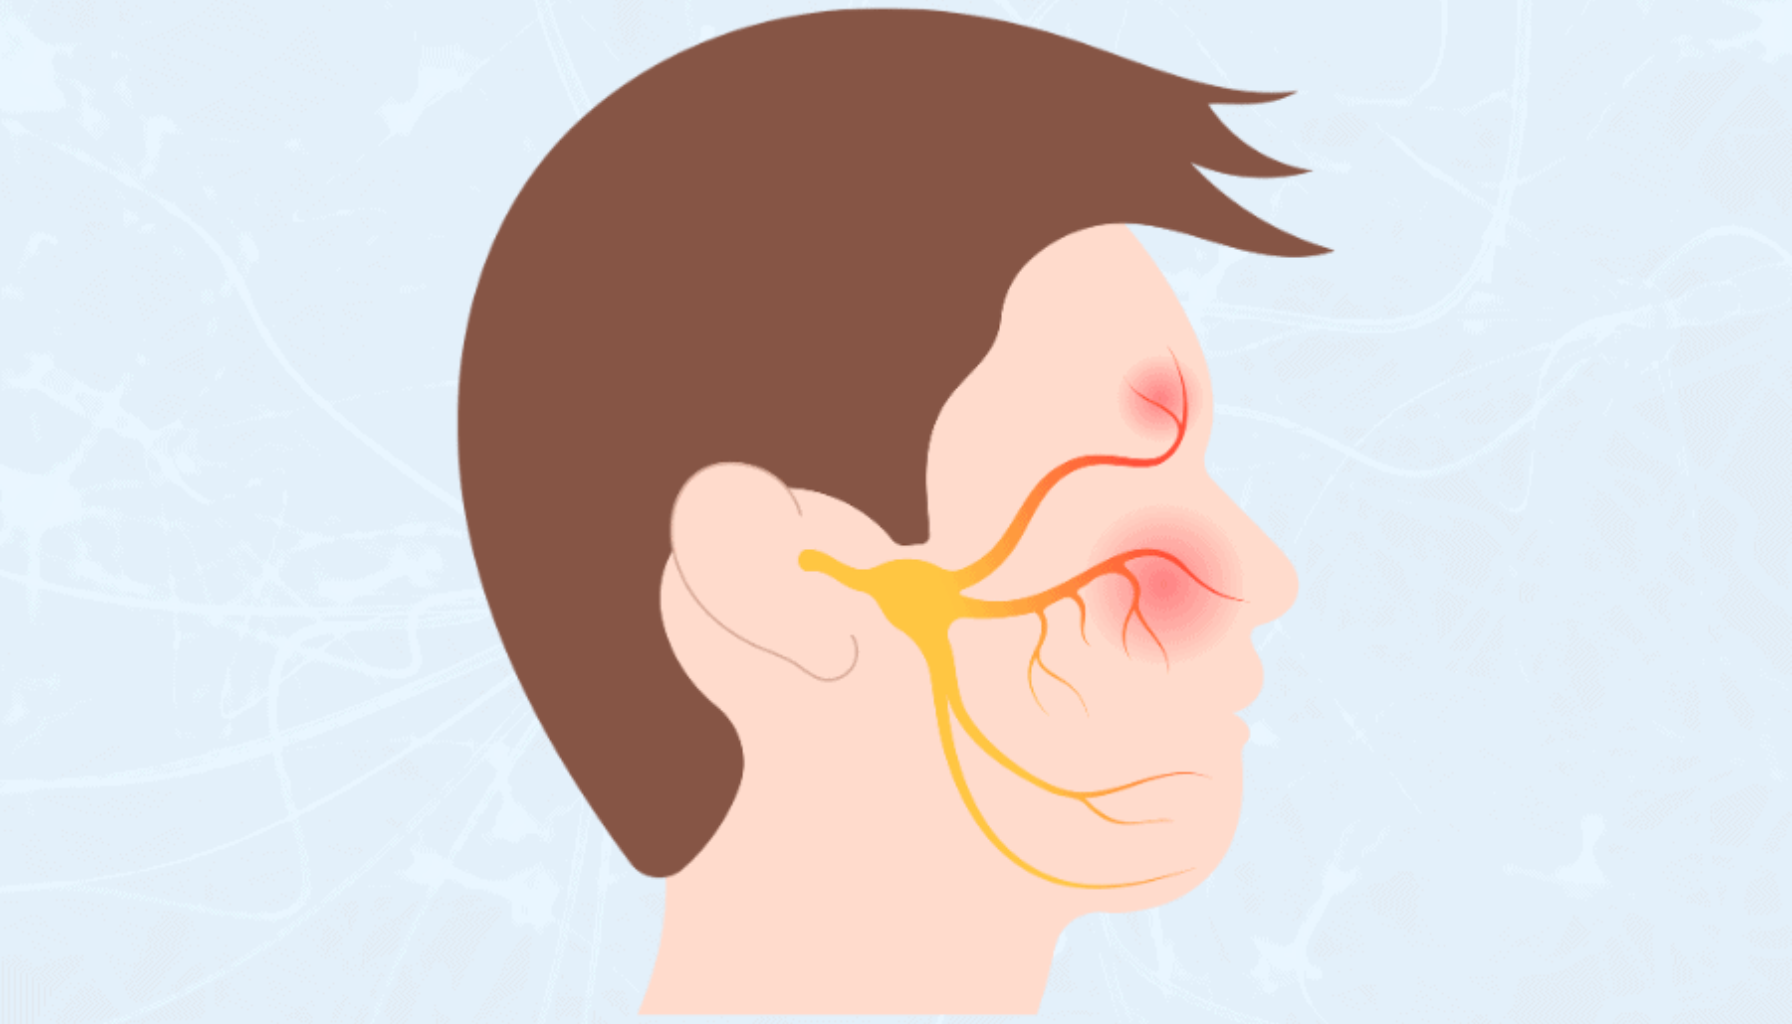

De mest karakteristiske symptomene er smertefulle munnsår som gjør det vanskelig å spise, drikke eller snakke. Før sårene bryter ut, kan man merke svie eller prikking i området. Tilstanden kan utløses av flere faktorer, inkludert stress, vitaminmangel, hormonelle endringer og visse matvarer som sitrus eller krydret mat. Mekanisk irritasjon, som bitt i kinn eller tannregulering, kan også spille en rolle. Hos noen pasienter er after tilbakevendende uten klar årsak. Det er derfor viktig å kartlegge mulige utløsende faktorer for å kunne forebygge fremtidige utbrudd.